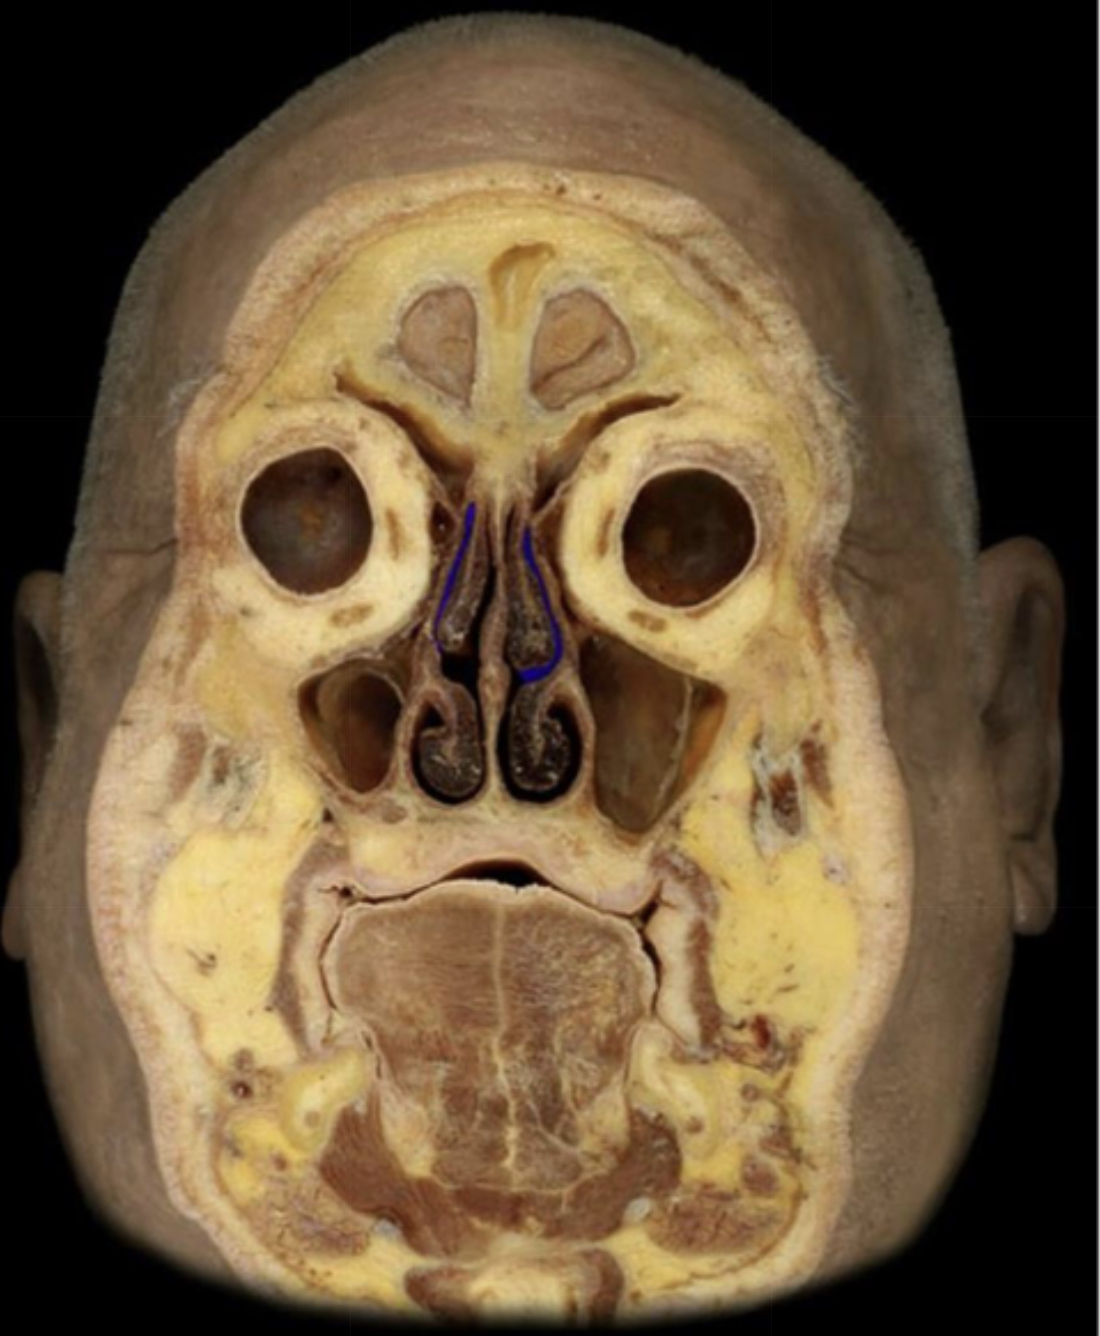

What structure is highlighted in blue?

Frontonasal duct